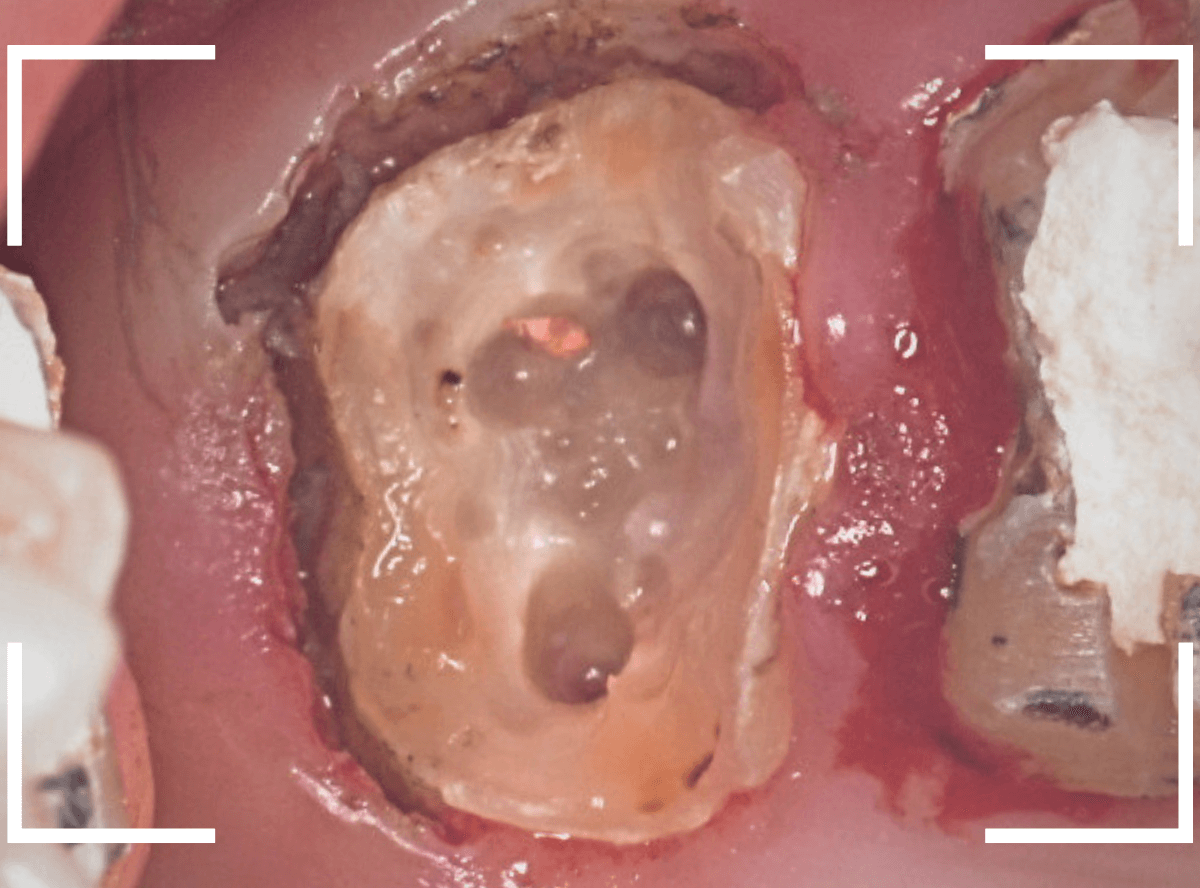

Case.2

神経の治療後に、土台を入れたまま放置をしてしまった患者さんです。

虫歯が歯肉の中まで入り込んでしまっていて、歯肉も腫れてしまっています。

神経を取ってしまっているので、どんなに虫歯が進んでも痛みもなくご自身では状況に全く気づけませんし、金属の土台(メタルコア)が入っているため、レントゲン写真でもどの程度まで虫歯が進んでいるのかわからず、慎重に土台を外して調べてみるしかありません。

土台を全て外したところです。

ギリギリ修復可能な歯の状態と判断して、治療を進めます。

歯を覆っている歯肉を麻酔をして除去してしっかりと歯の表面を出し、虫歯も全て取り切りました。

新しくファイバーコアを製作するために、型どりをします。